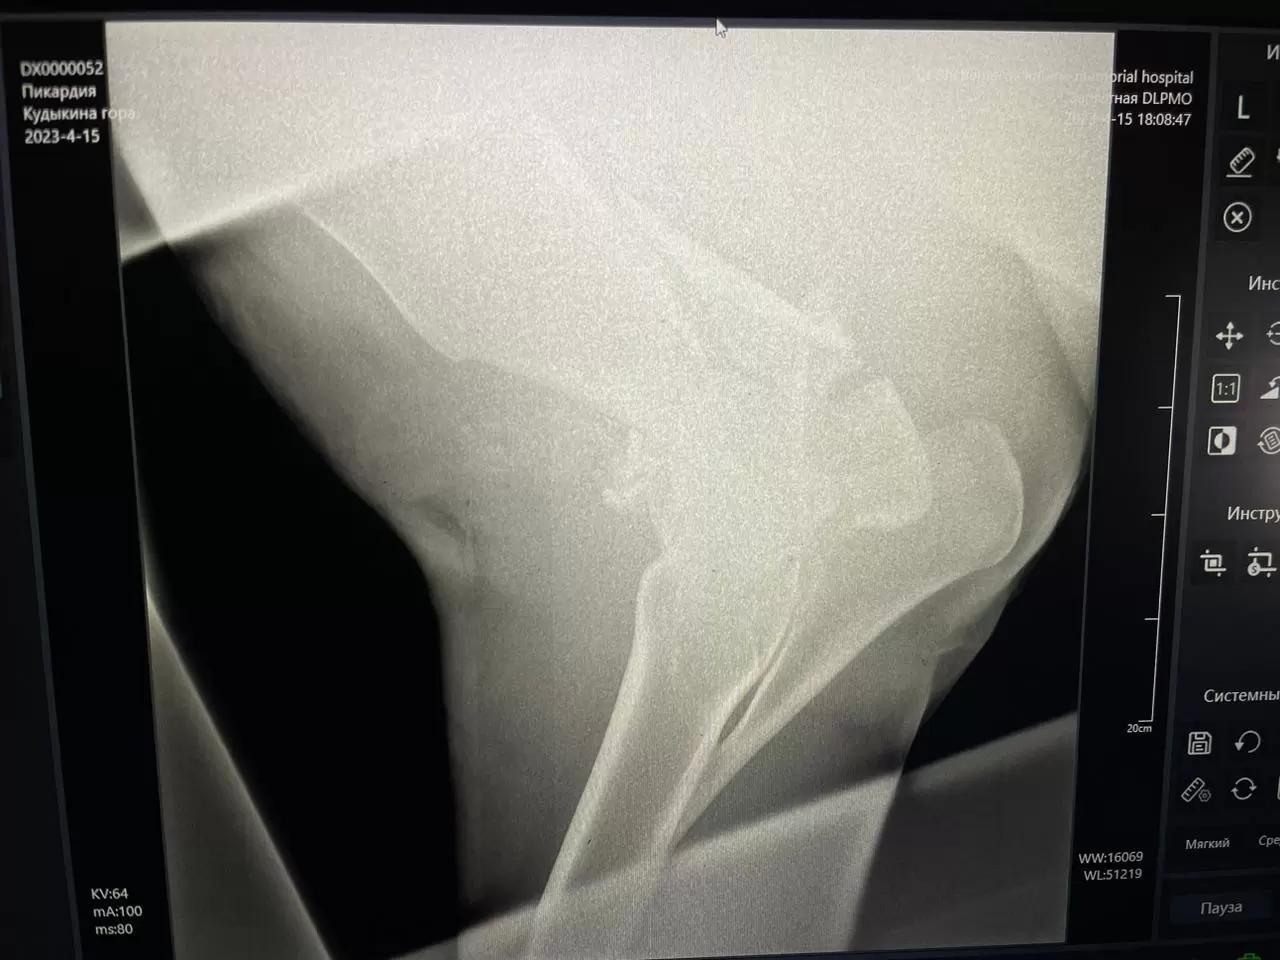

С другой стороны, мучить тоже сильно не хочется... Прошу совета и опыта! На фото 4 дня с перелома предплечья.

По лечению: Пенбекс, Келапрофен, гель Травматин, Гамавит, вторую ногу бинтуем и массаж. Кормление Втм, будем на мюсли диетические переходить. Кобыла активно ест, температура 38,1... Думаем о подвесе и вариантах облегчения нагрузки. Она, конечно, не ложится.